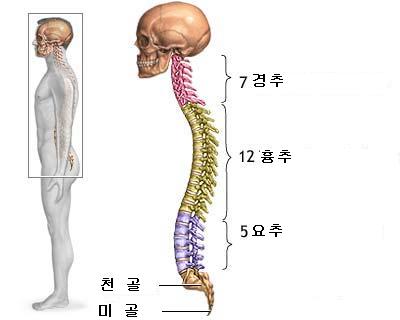

급성요추염좌 척추는 우리몸을 지탱하며 척추신경을 주관하는 중요한 역할을 하는 것으로 목(경추)7개, 등(흉추)12개, 허리(요추)5개, 천추와 꼬리뼈(미추)등약 32~34개의 추골로 이루어져 있다.